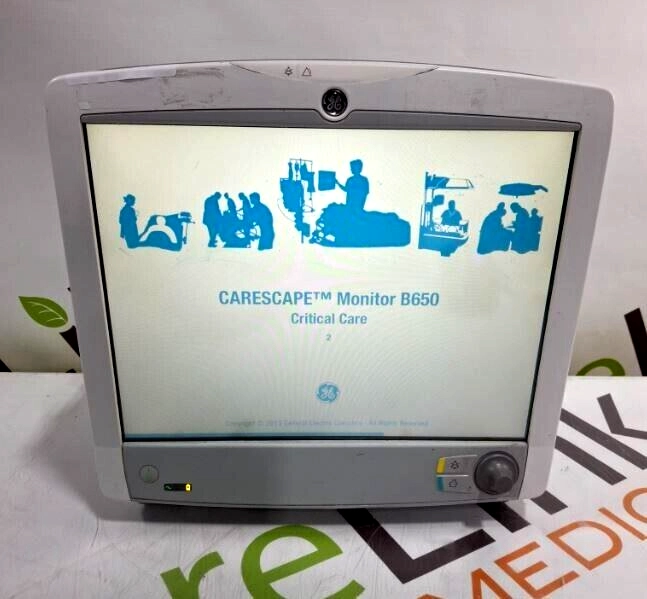

GE Healthcare Carescape B650 Patient Monitor

$618.00

USD

GE Healthcare Carescape B650 Patient Monitor

$618.00

USD